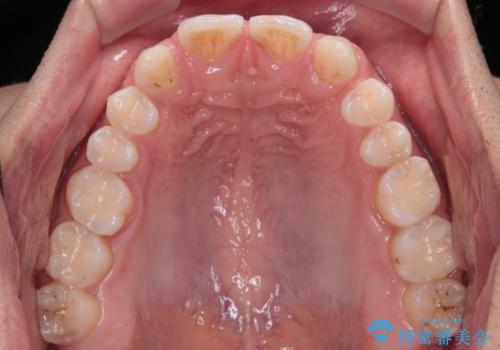

- 歯の欠損による前歯のすきっ歯を気にして来院された患者様です。

矯正治療かオールセラミックか、治療の選択がありましたが、熟考の末オールセラミッククラウンにて補綴することとしました。

ひとつひとつの歯の幅は非常に大きくなりましたが、手っ取り早く隙間が改善されたとのことで、大変満足していらっしゃいました。